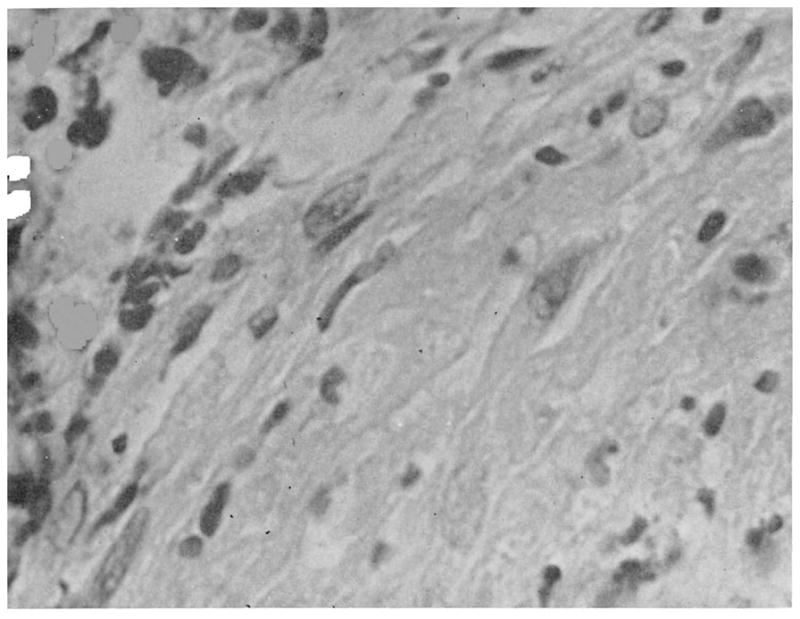

Changes in small blood vessels are obvious promptly with thawing. Using microangiography and transillumination techniques, these may evolve for weeks or months.5 There is an immediate, intense arterial vasoconstriction at the junction of uninvolved tissue with frozen tissue. Within a few hours, a demonstrable increase in vascularity occurs in the marginal zone, at the time this area becomes clinically erythematous. Some authors have described the opening of small arteriovenous shunts in this region.20 Flow rate is reduced and intravascular sludging is observed. Within three days multiple small areas of stenosis, or frank, sharply delineated occlusions have been observed microangiographically5 within the previously-frozen area. Tubular filling defects which are thought to be thrombi can be demonstrated in both arteries and veins. By the tenth day these either regress or proceed to stenosis or occlusion of the vessels. During the ensuing weeks, both arteries and veins disappear from the microangiography pattern, presumably due to late thrombosis. The resulting destruction of vascular architecture is partially compensated by the previously mentioned increase in marginal blood supply from which new branches may bud into the formerly frozen area.6 However, in six to twelve weeks such new networks undergo involution and, if the injured area does not undergo necrosis, it is left with a distorted and cross-sectionally reduced vascular pattern.5 Histologic sections at various stages in the above sequence show edema and small-vessel thrombi which are often fibrinoid in character (Fig. 5), and later areas of local arteritis or intimal proliferative thickening (Fig. 6).

Fig. 5.

Arterial injury, 1 month after frostbite. Lumen is at upper left. Note intramural edema, disruption of epithelieal lining, and thrombus.